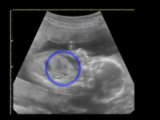

Read Fetal Sonographic Biometry PDF Online